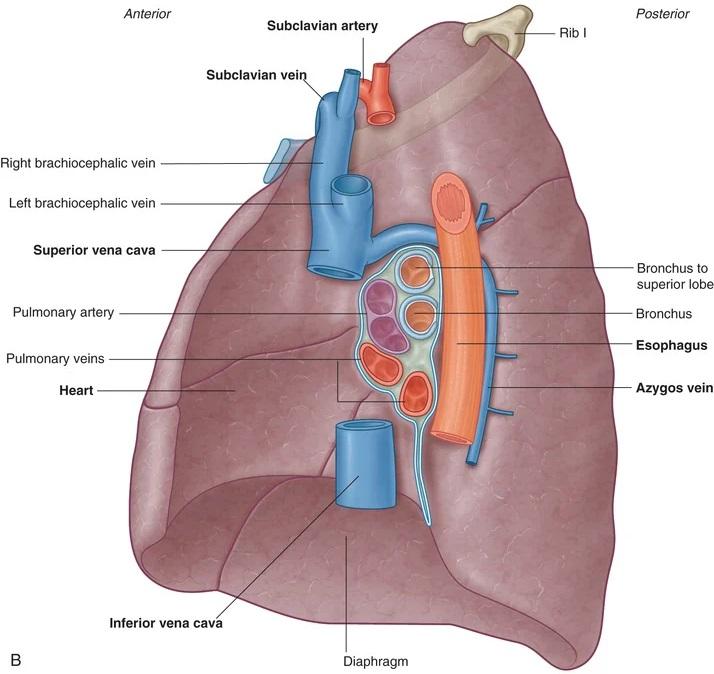

Fig 3.38a: Longhilus rechts

v. cava superior v. azygos a. pulmonalis dextra vv. pulmonales (zwart) bronchus

Grays: Fig 3.45